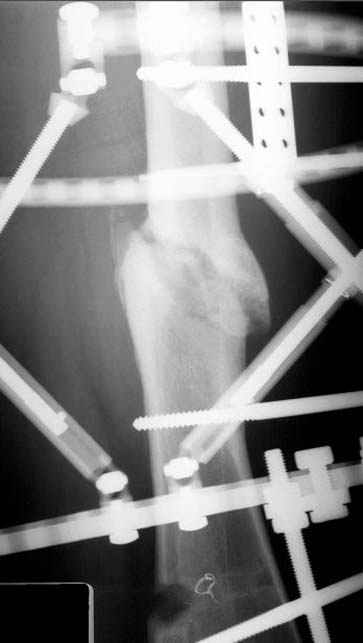

Отправитель: Djoldas Kuldjanov 23 Ноябрь 2004, 18:21

пластическая модель; и коррекция бедра аппаратом Илизарова.

Имею другие снимки тоже, получится как отчет о моей работе.

Отправитель: Evgueny Tschekashkin 23 Ноябрь 2004, 21:28

Почему не замена гвоздя с рассверливанием, а аппарат?

Отправитель: Alexander Chelnokov 23 Ноябрь 2004, 21:29

Попробую угадать - была инфекция?

Отправитель: Evgueny Tschekashkin 24 Ноябрь 2004, 21:09

хотя даже если бы и инфекция , то nail exchange с рассверливанием канала - вариант дебрайдмента) Я думаю, что последовательность развития событий:

Узкий к-м канал - тонкий гвоздь- усталостный перелом дистальных винтов - развитие нестабильности и как ее результат остеолиз вокруг гвоздя - деформация анатомической оси бедра. Похоже, что я понял почему аппарат, а не новый гвоздь:-)